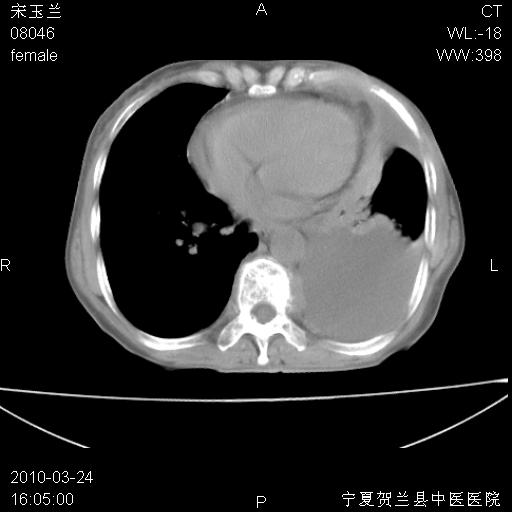

以下是引用zxl51642在2010-3-24 18:49:00的发言:[br]结合乳腺癌术后病史,考虑双肺及纵隔淋巴结多发转移、左侧胸膜转移并左侧大量胸水、左下肺膨胀不全。